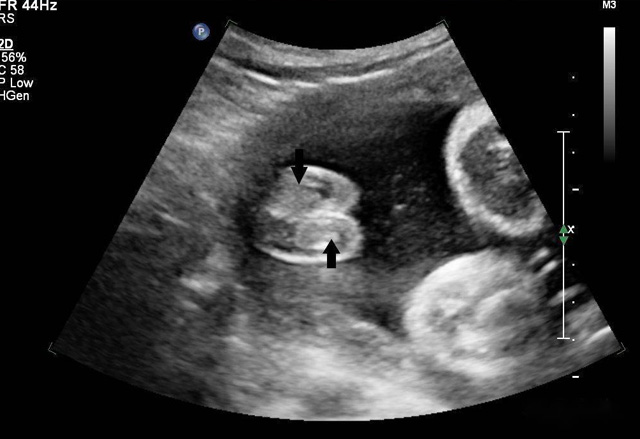

動態(tài)三維超聲成像有時間因素(心動周期)三維超聲成像分為靜態(tài)三維超聲成像和動態(tài)三維超聲成像,整體成像法重建感區(qū)域?qū)崟r活動的三維圖像,稱為四維超聲心動。

三維超聲技術(shù)可用于心臟、腹腔、婦科、產(chǎn)科、小器官、血栓、血管成像等多方面。